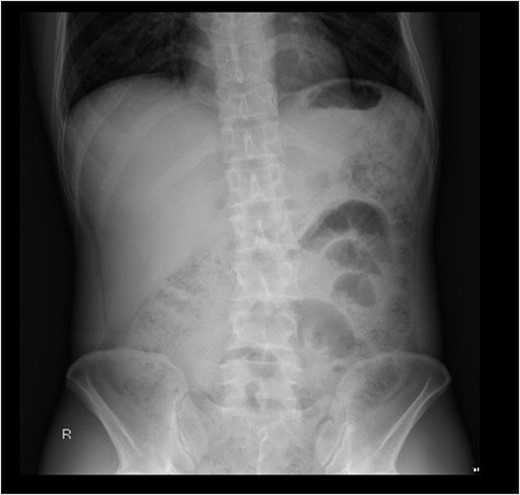

On initial presentation the patient was pyrexial, with a fever of 38.9 °C, but haemodynamically stable. Abdominal examination revealed diffuse peritonitis. Laboratory results showed a mild lecuocytosis (white cell count 10.5 g/L) but were otherwise within normal limits. Plain film X-ray of his abdomen was suggestive of pneumoperitoneum (see Fig. 1). A clinical diagnosis of suspected perforated duodenal ulcer was made and the patient was initially resuscitated with intravenous fluids and broad-spectrum antibiotics while a computed tomography (CT) scan of his abdomen and pelvis was arranged. The CT revealed showed a small rod-shaped radiopaque object in a thickened small bowel loop in the hypogastric region, with associated free abdominal fluid and air (see Fig. 2). This was concerning for small bowel perforation due to a foreign body.